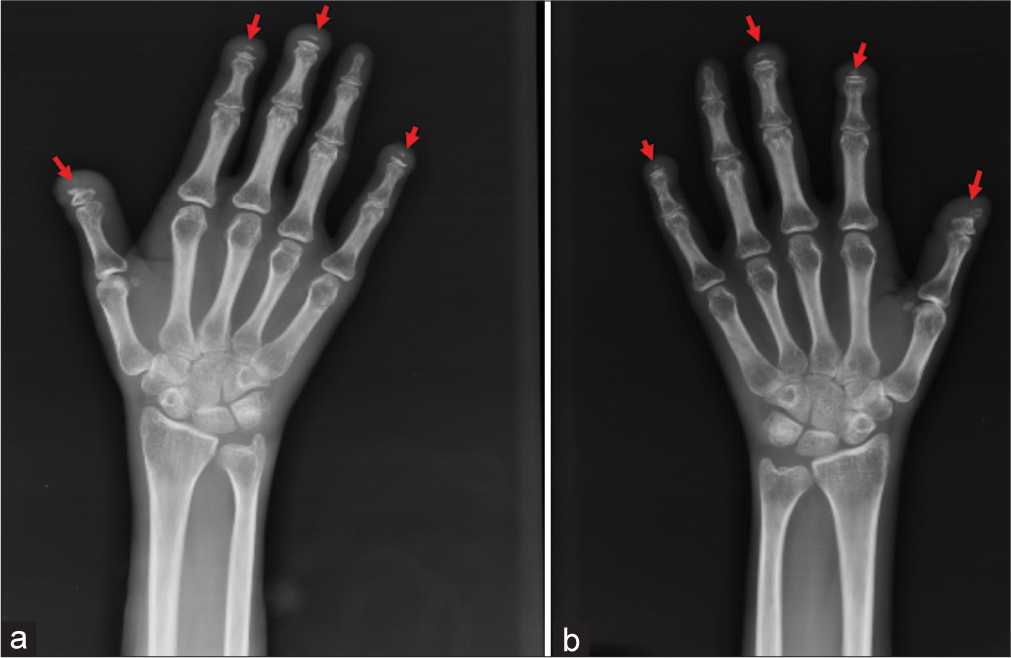

- Wormian bones: Extra bones within the cranial sutures.

- Premature fusion of the cranial sutures (craniosynostosis): Leading to abnormal skull shape and potentially increased intracranial pressure.

- Platybasia: Flattening of the skull base.

- Cranial imaging (CT or MRI) to evaluate cranial suture abnormalities or platybasia.